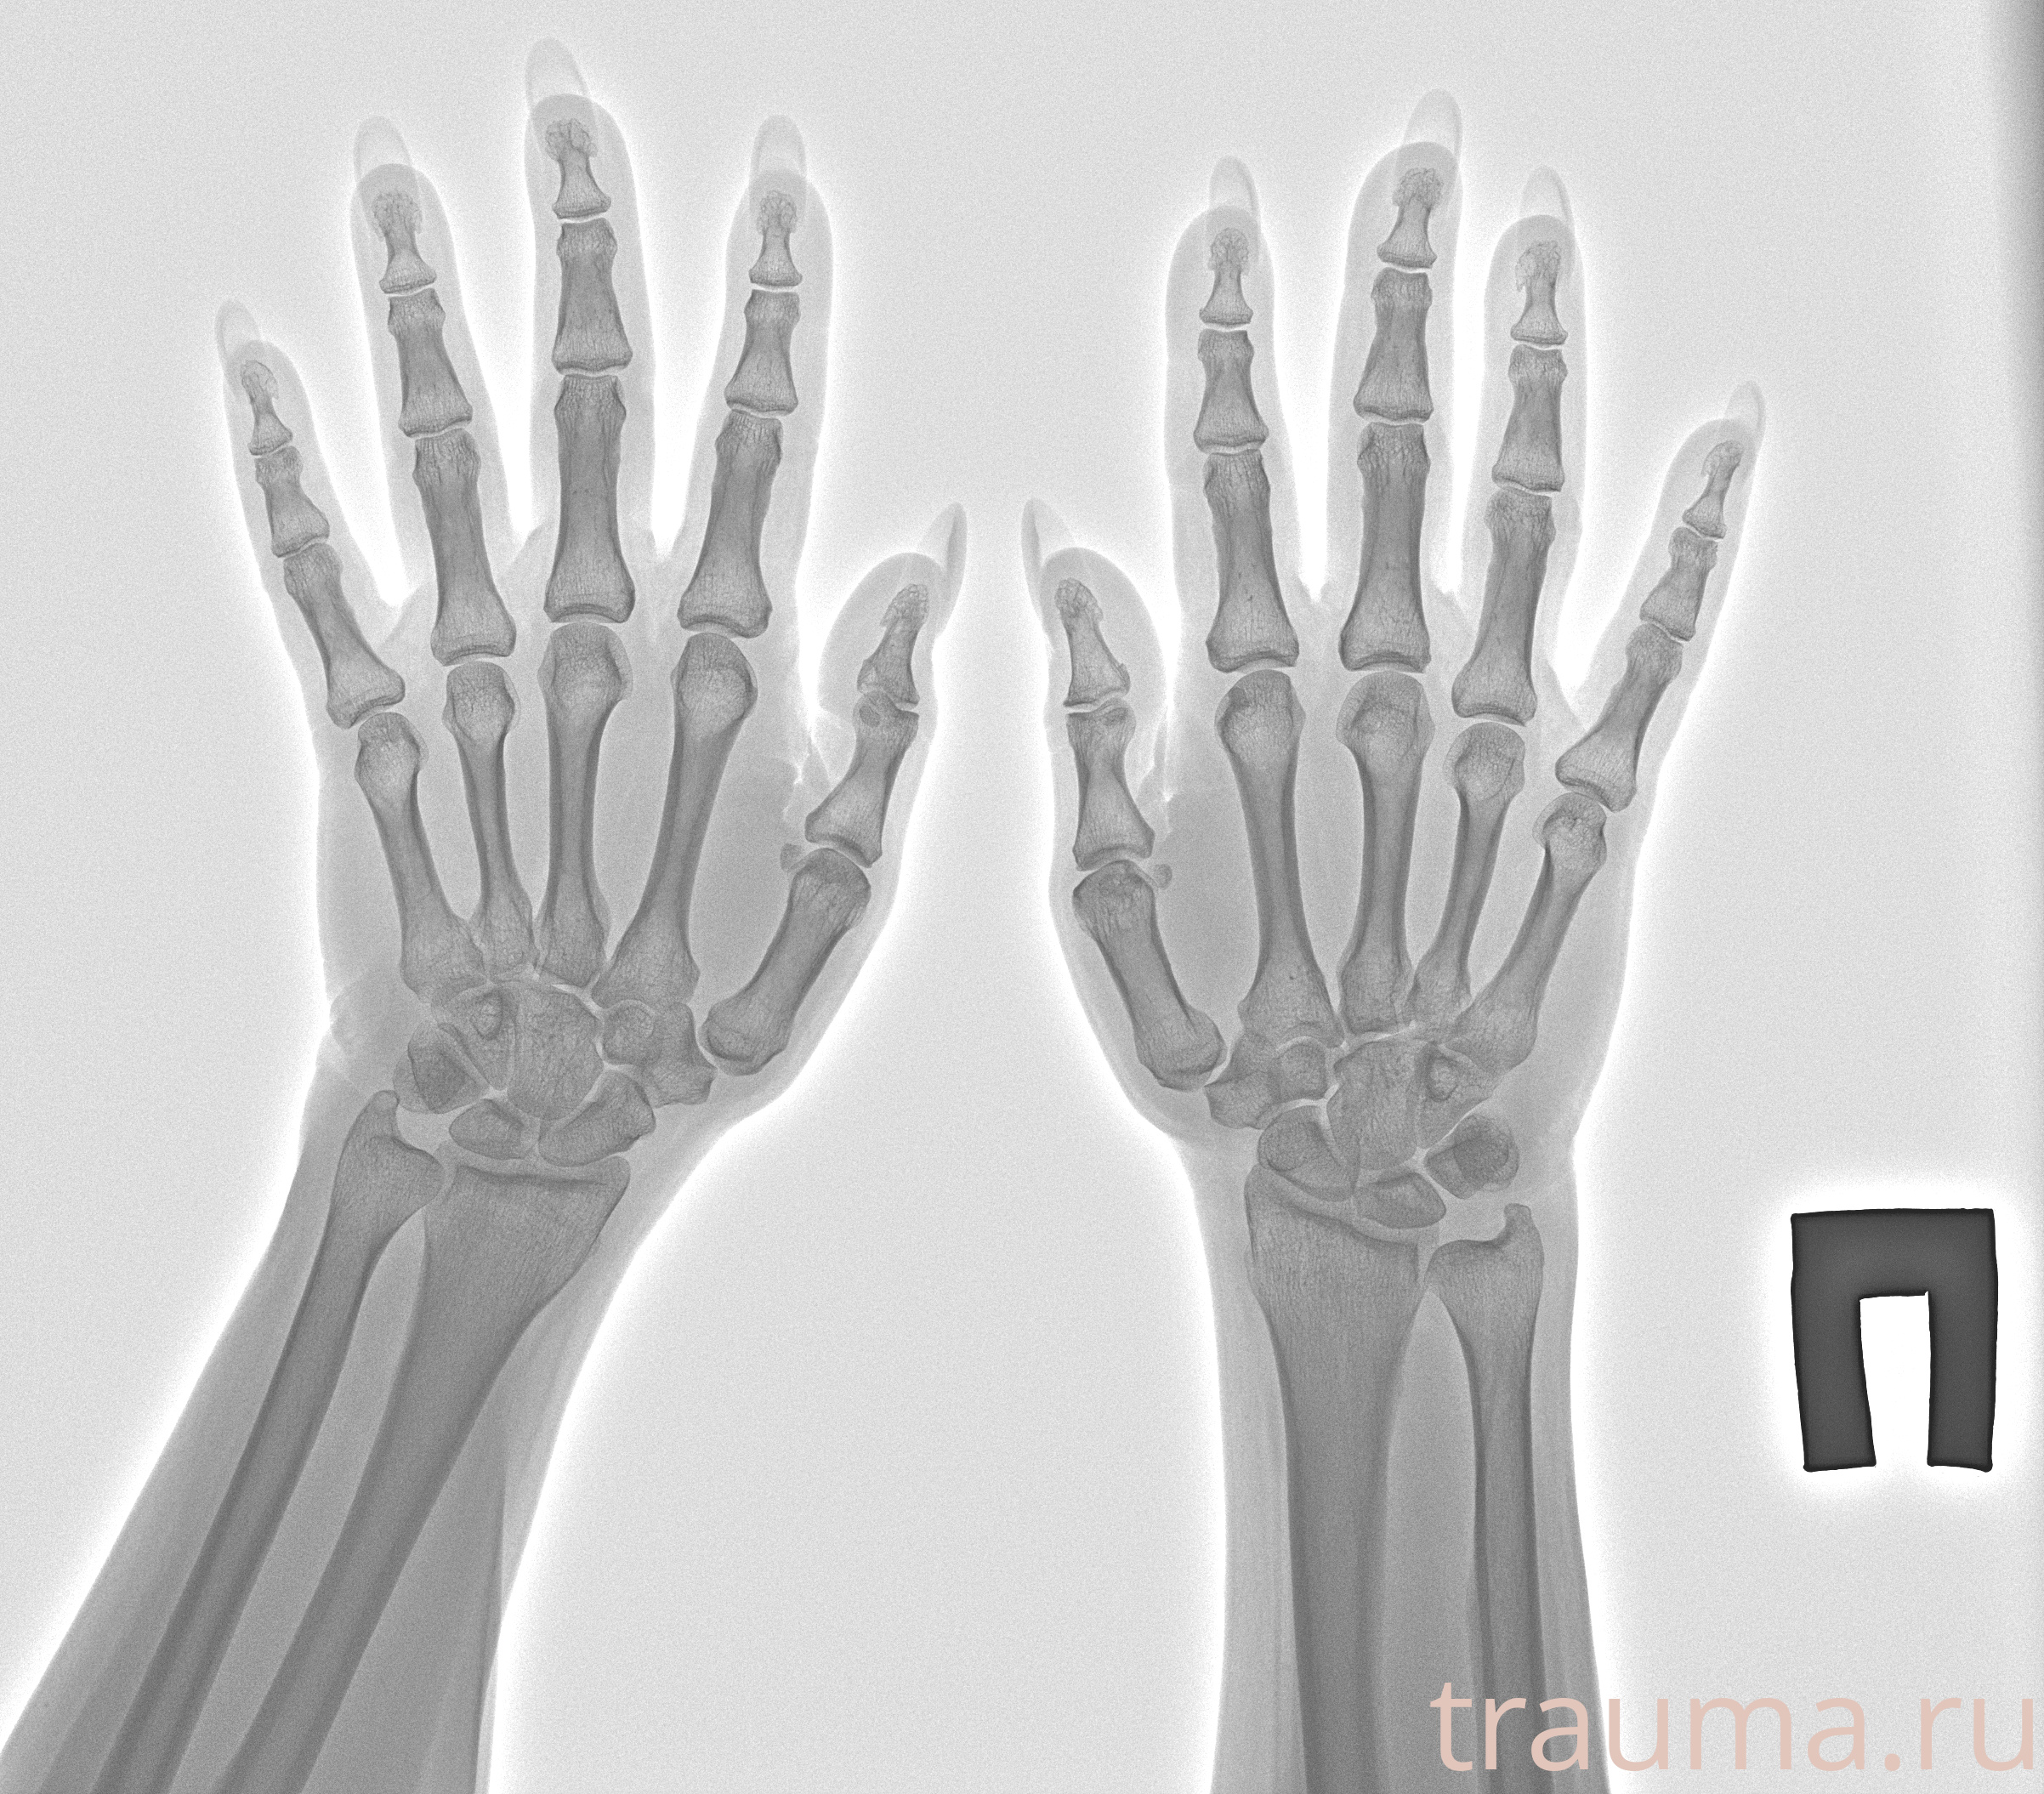

Рентгенограммы

Рентген на дому: по вашему адресу приезжает врач-рентгенолог, травматолог-ортопед с мобильным рентгеновским аппаратом, проводит диагностику травмы или заболевания, делает необходимые рентгенограммы, дает рекомендации по дальнейшему лечению. Получить качественные снимки в домашних условиях возможно благодаря уникальной методике, разработанной МосРентген Центром для института  Склифосовского